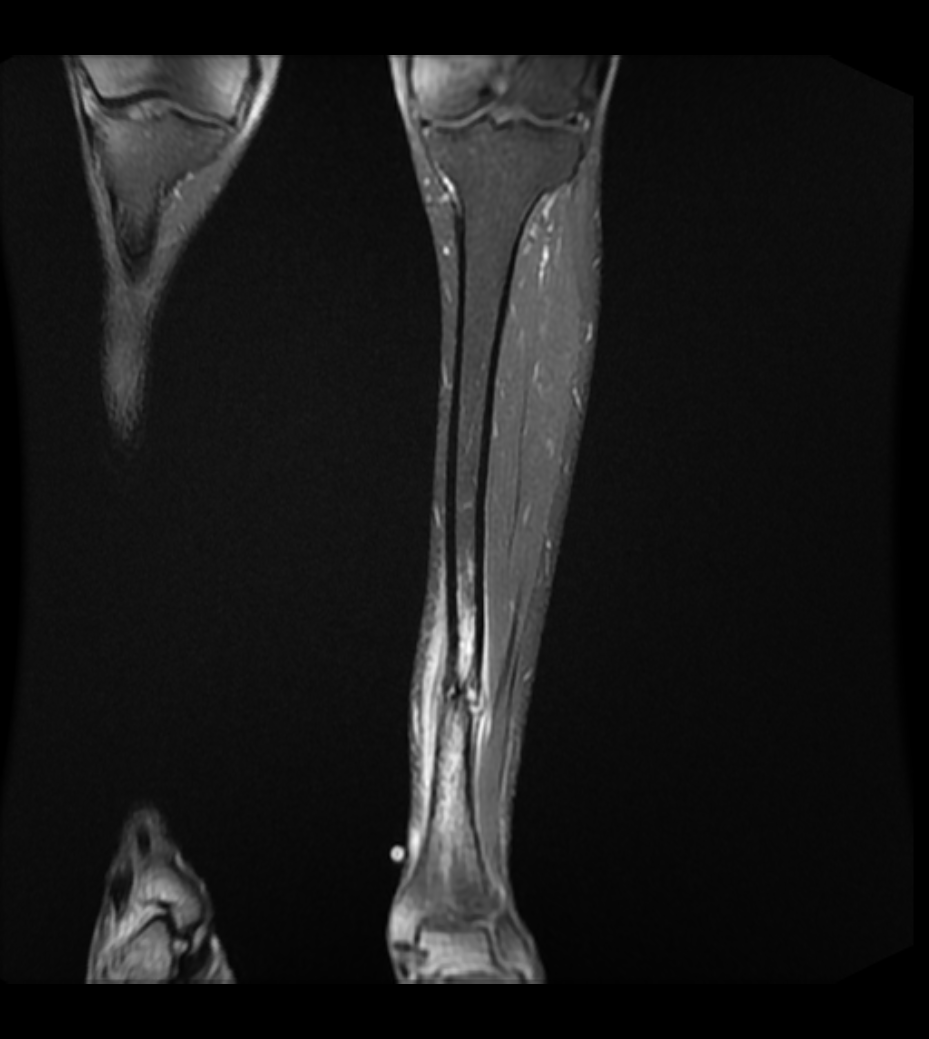

From mavink.com

Tibial Stress Fracture Mri Stress Fracture Tibia Not Healing Diagnosis can often be made on. This topic review will discuss stress fractures of the tibia and fibula in adults and children. Learn how to prevent and treat them. Stress fractures take longer to heal and may require a brace, a walking boot, and crutches. Most people fully recover from shin splints and avoid developing stress fractures. A tibial shaft. Stress Fracture Tibia Not Healing.